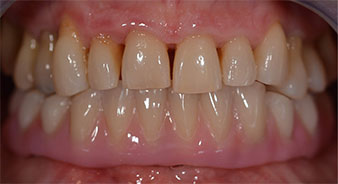

След това е взет отпечатък и е определена захапката на пациента, за да може зъботехникът незабавно да започне изработването на временната протеза. Протезата е поставена в същия ден (Фиг. 17 и 18).

След изчакване на необходимото време за осеоинтеграция, финалният отпечатък на имплантите е свален и следователно е изработена финалната протеза (Фиг. 19 и 20). В този момент, лекарят по дентална медицина и пациентът могат да обсъдят дали да използват керамични или пластмасови фасети и циркониева или метална рамка. В този случай, екипът на д-р Паску избира пластмасови фасети, имайки предвид неясната прогноза относно частичното обеззъбяване в челюстта и фактът, че зъб 24 е прорастнал. Този вид протеза обикновено е по-лесна за адаптиране и впоследствие може да бъде променяна спрямо новата ситуация в челюстта.